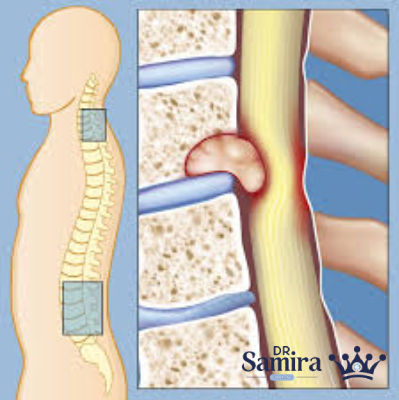

میکسو پاپیلاری اپاندیمومای نخاع یکی از تومورهای نسبتا نادر دستگاه عصبی مرکزی است که بیشتر در ناحیه پایین ستون فقرات، به خصوص در قسمت مخروط انتهایی نخاع و رشته باریک انتهایی آن که به نام فیلوم ترمیناله شناخته میشود، دیده میشود. این تومور از سلولهایی به وجود میآید که در حالت طبیعی کانال مرکزی نخاع را میپوشانند و مسئول تولید و تنظیم مایع مغزی–نخاعی هستند.

درد یا احساس تیر کشیدن پاها (سیاتیک): به دلیل فشار تومور بر ریشههای عصبی در ناحیه کمری ایجاد میشود.

ضعف یا بی حسی در پاها: بیمار ممکن است به تدریج احساس کند توانایی راه رفتن یا کنترل عضلات پا کاهش یافته است.

با این حال، گاهی به دلیل نزدیکی تومور به رشتههای عصبی حیاتی، امکان برداشت کامل وجود ندارد، زیرا ممکن است آسیب به عصب منجر به فلج یا بی اختیاری شود.